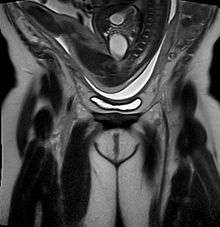

Frank breech, William Smellie, 1792 | |

- A frank breech (otherwise known as an extended breech) is where the baby’s legs are up next to its abdomen, with its knees straight and its feet next to its ears. This is the most common type of breech.